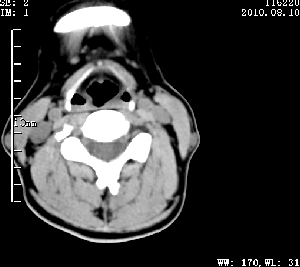

标题: CT28317:病人近几天无意间发现颈部肿块。

甲状腺左叶局限性结节性甲状腺肿可能。建议增强扫描。

病变边界清楚,周围间隙清晰,甲状腺左叶(甲状旁腺?)肿大,右叶甲状腺腺瘤。

病变边界清楚,周围间隙清晰,左叶甲状腺肿大,右叶甲状腺小腺瘤。